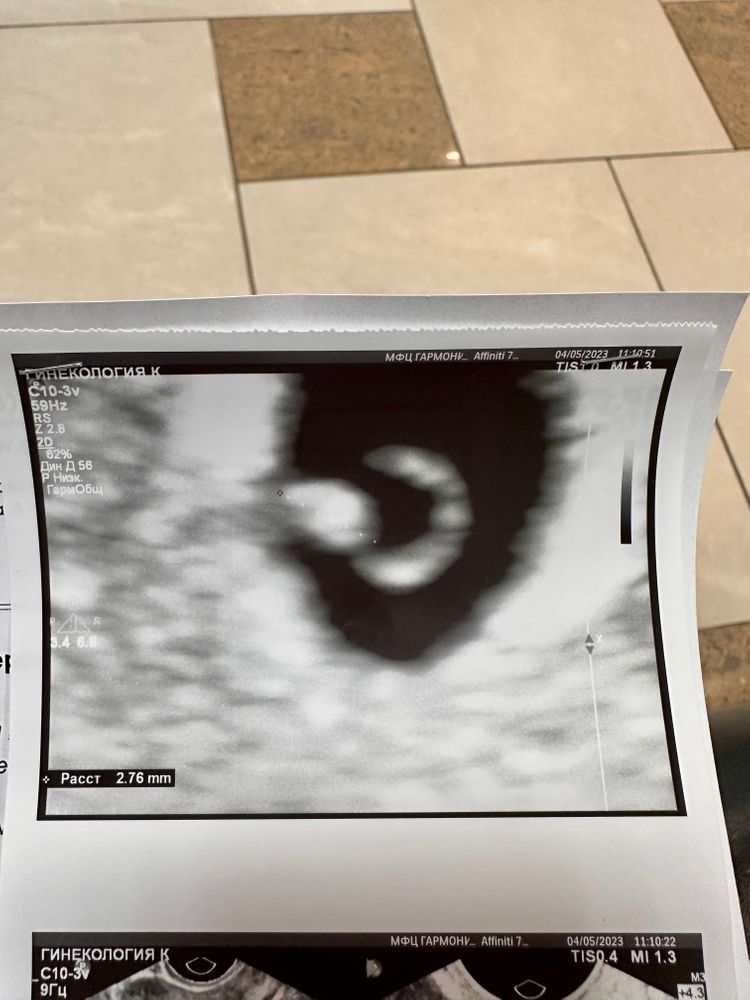

ФолликулометрияНашли эмбриончик и пульсацию. Колечко с бриллиантиком увидели 💍.

Нашли эмбриончик и пульсацию. Колечко с бриллиантиком увидели 💍.